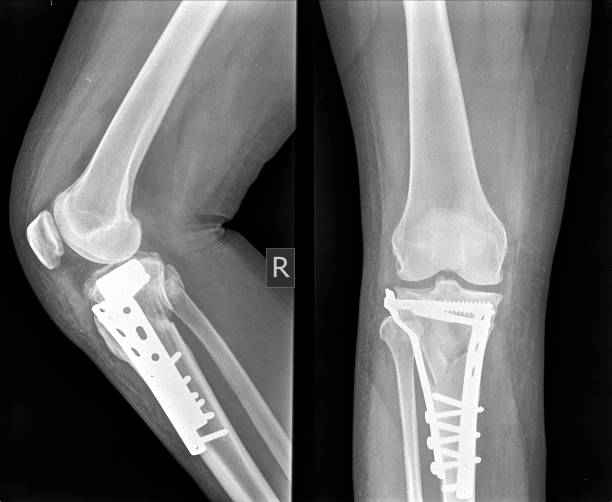

Implant Removal Major & Minior Surgeries

Implant removal surgeries, whether major or minor, entail the extraction of hardware like screws, plates, rods, or other implants that were previously inserted to stabilize bones or joints during a surgical procedure. Here’s a breakdown of the process including indications, procedure, and recovery. Implant removal surgeries may present complications such as infection, bleeding, nerve or tissue damage. These surgeries can range from minor procedures performed to alleviate discomfort or irritation to more complex major surgeries required to address complications or issues associated with the original implantation. The specific approach utilized depends on the patient’s condition, the reason for implant removal, and any associated complications.

Open Reduction Dislocation Major & Minior Surgeries (ORIF)

Open reduction dislocation surgery, also known as ORIF (Open Reduction Internal Fixation), is a surgical procedure utilized to repair complex joint dislocations. It is a more invasive approach compared to closed reduction, which involves manipulating the bones back into place without surgery. Open reduction and internal fixation (ORIF) is performed to realign and stabilize displaced bones or joints that cannot be properly repositioned through closed reduction alone. These surgeries are typically recommended when closed reduction techniques fail to adequately realign the bones or joints, or when there are complicating factors such as fractures that cannot be addressed non-surgically.

Common conditions requiring ORIF include severe fractures, dislocations, or joint instability that cannot be managed conservatively. ORIF surgery is a major procedure used to treat severe fractures, dislocations, or joint instability by realigning and stabilizing the bones or joint with internal fixation devices. While it carries some risks, it can provide significant benefits in terms of restoring function and mobility to the affected limb or joint.